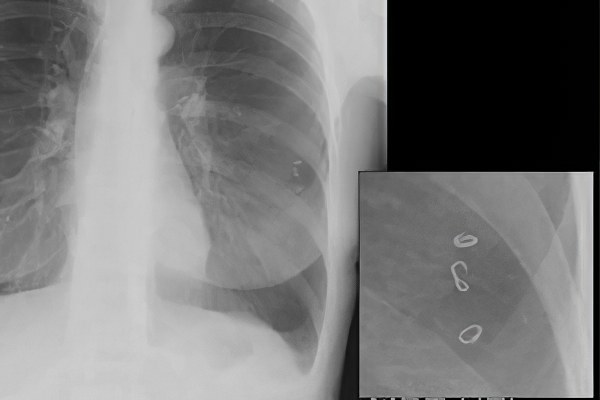

Рентгенография при аскаридозе

Метод используется для выявления изменений в легких и кишечнике. Это доступный и недорогой способ диагностики, который применяется при первых подозрениях на аскаридоз.

Изменения, которые можно увидеть на рентгеновских снимках:

• Рентгенография брюшной полости – позволяет обнаружить скопление кала и газа при кишечной непроходимости. Этот метод помогает отличить аскаридоз от других заболеваний желудочно-кишечного тракта. Однако сами аскариды на рентгеновских снимках не видны.

• Рентгенография грудной клетки – на этом снимке можно заметить изменения в тканях во время легочной стадии аскаридоза (в течение первых 10 дней). Выявляется летучий инфильтрат Леффлера, который меняет свое местоположение через несколько дней. Различия между аскаридозом и пневмонией, а также новообразованиями в легких становятся очевидными при повторной рентгенографии, когда скопления паразитов перемещаются в другую область. Пневмония может развиваться у пациентов с ослабленным иммунитетом как вторичное осложнение основного заболевания.